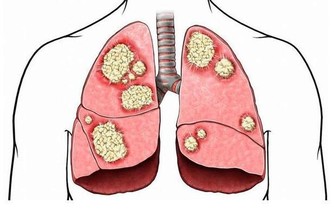

防治心腦血管疾病更要吃它

洋蔥一種有血管擴張功能的食物, 能夠軟化血管, 促進引起血壓升高的鈉鹽等物質的排泄, 因此能調節血脂, 降壓和預防血栓形成, 很好的預防和輔助治療心臟病。

哈佛醫學院心臟科教授克多格爾威治博士指出, 每天生吃半個洋蔥, 或喝等量的洋蔥汁, 平均可增加心臟病人約30%的高密度脂蛋白膽固醇HDL含量(HDL:有助於預防動脈粥狀硬化的膽固醇, 就是「好」的膽固醇。 )

洋蔥中所含有山奈酚和檞皮黃酮等成分, 能夠阻止癌細胞的血管生成, 可防治乳癌、胃癌及其他癌症的發生。